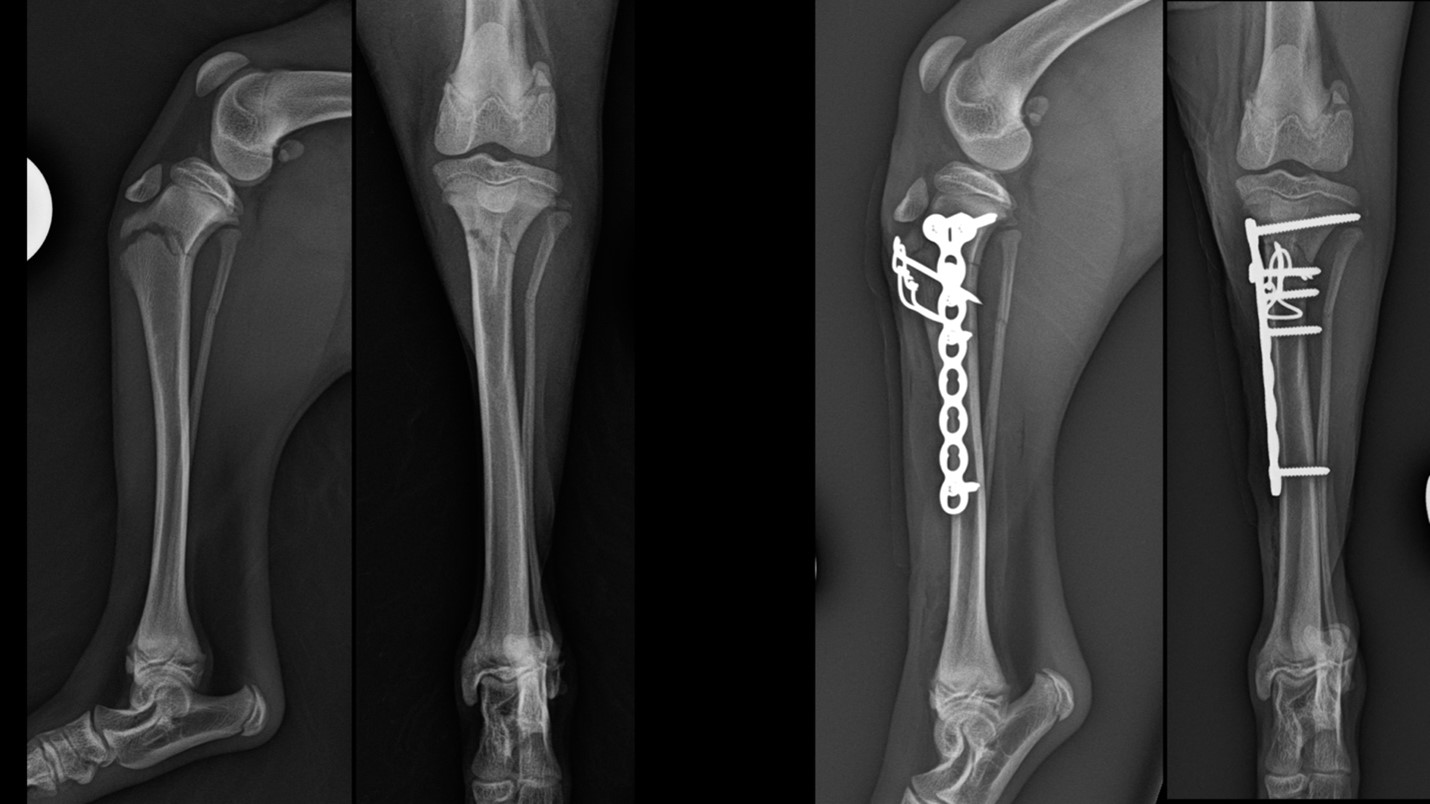

Falling from heights is one classic example. In fact, among the most common conditions that we as veterinarians encounter in toy dog breeds—are radius and ulna fractures secondary to falls. Their bones are comparably small and fragile, and because these animals often live what you might call a high-rise existence, with large couches to jump off and children who cuddle them and let them leap from their arms, this is a very common pathology.

Toy breed dogs have bones susceptible to low energy fractures. Cross sectional geometric evaluation has identified that the antibrachii of toy breed dogsare more susceptible to fracture when proportionally loaded than those of large breed dogs due to morphological differences. Many of these fractures are very distal and commonly approach a juxta-articular configuration—breaks that occur just above the joint—creating practical challenges for surgeons with finite bone stock to navigate for fixation.

Another challenge, is the fact that the perfusion of radius and ulna fractures in toy breeds is different to what we see in bigger dogs. Bones are supplied with blood via the central canal as well as from the muscles around the bone and the periosteum—the network of vessels that run over the periphery of the bone. In small-breed dogs, a decrease in vascular density at the distal diaphyseal-metaphyseal junction compared with large-breed dogs has been documented. This regional association suggests that a decreased vascular supply in the distal radius may contribute to a higher frequency of delayed union and nonunion in smaller dogs. When the location of a break is very low down on the bone, there are very few muscles present—commonly referred to as a poor soft tissue envelope. So, having a strategy to accommodate and plan for that is important.

Any implant we may want to use must be correspondingly small. The implants that have traditionally been available have not always necessarily been compatible with the kind of bone size that is characteristic of toy breed dogs. There has been a relative explosion of smaller implants from a range of different veterinary implant manufactures from around the world in recent years.

For instance, in 2020, the AO Technical Commission, gained approval for the Synthes mini fragment plates. These plates are smaller than traditional ones and the tolerances and precision required for successful application exist on a very narrow spectrum. And it is of course equally important for colleagues to understand that these new implants exist and under which circumstances they should select a certain size implant over another. Locking and non locking internal fixation systems are now accessible from as small as 1.0mm.